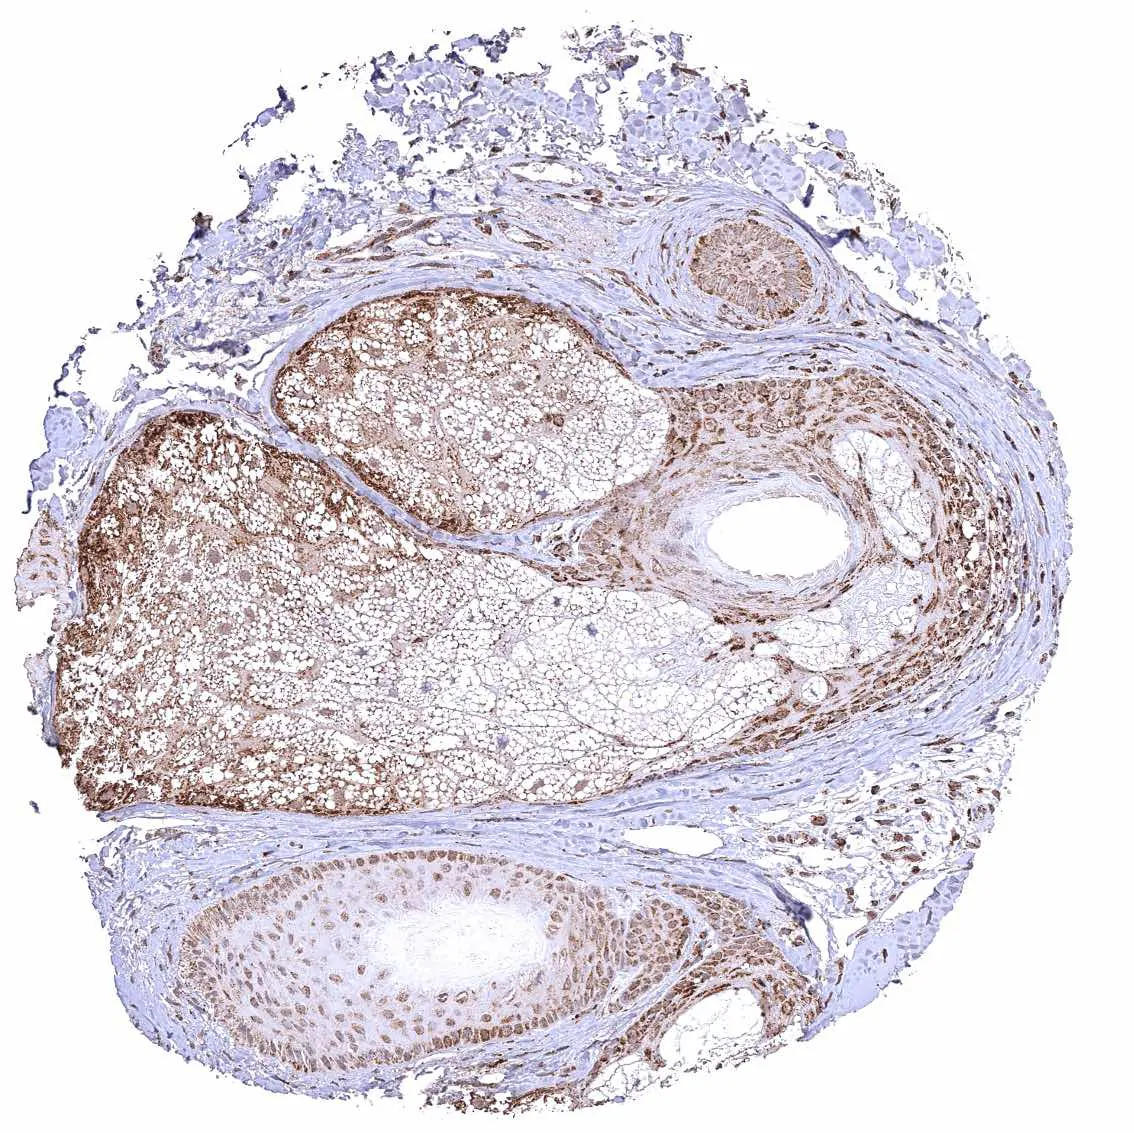

Skin, hairfollicel and sebaceous glands – Distinct cytoplasmic ATP5J staining of all cell types of hair follicles but staining is particularly weak in sebaceous glandular cells.